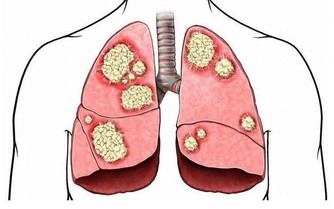

自身免疫系統出了問題

很多患者剛開始感覺關節疼,都會覺得是骨骼上的問題,等到檢查後才發現是免疫系統疾病,比如說之前有一位中年女性患者,病史為銀屑病,近期發現中指關節腫大,以為是關節炎,結果詳細檢查後發現是紅斑狼瘡,此外,強直性脊柱炎、銀屑病、風濕都可能導致關節疼痛。